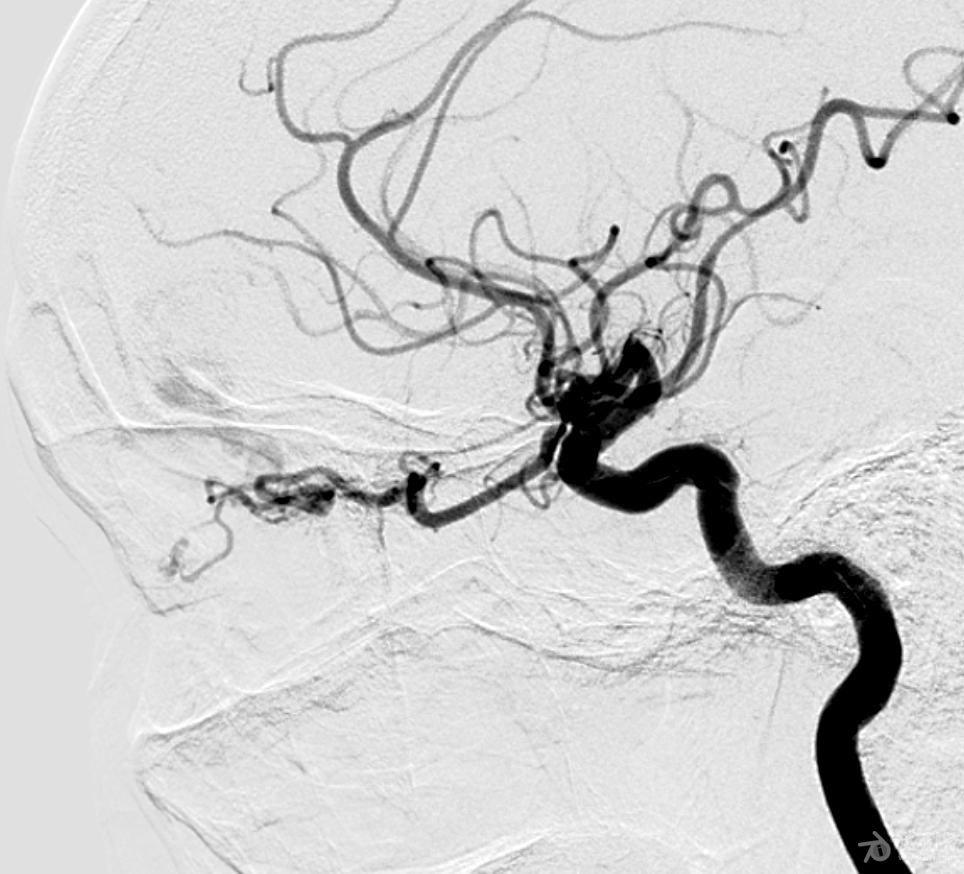

一例硬脑膜动静脉瘘病人介入治疗

医患沟通 | 脑动静脉瘘,术前可以这样沟通